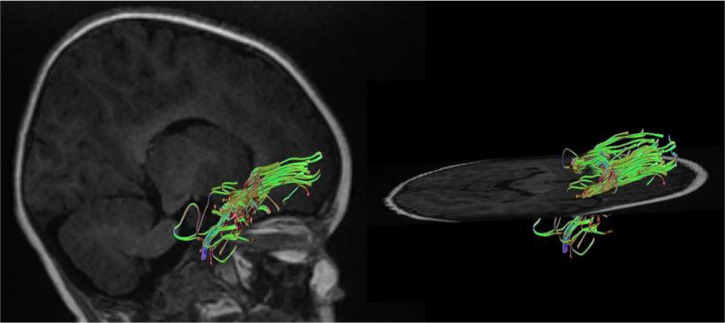

Methods: Twenty-two children including 11 subjects with SNHL aged 1-4 years and 11 healthy children were examined as controls. Then, DTI-derived parameters, such as fractional anisotropy (FA), mean diffusivity (MD), axial diffusivity (AxD), and radial diffusivity (RD), and volume of fiber tracts were extracted from the inferior longitudinal fasciculus, acoustic radiation, and uncinate fasciculus.

Results: The results showed an increase in MD, RD, and AxD as well as a decrease in FA, volume, and diameter of auditory-pathway-related fiber tracts. Interestingly, there was an increase in the FA of acoustic radiation.